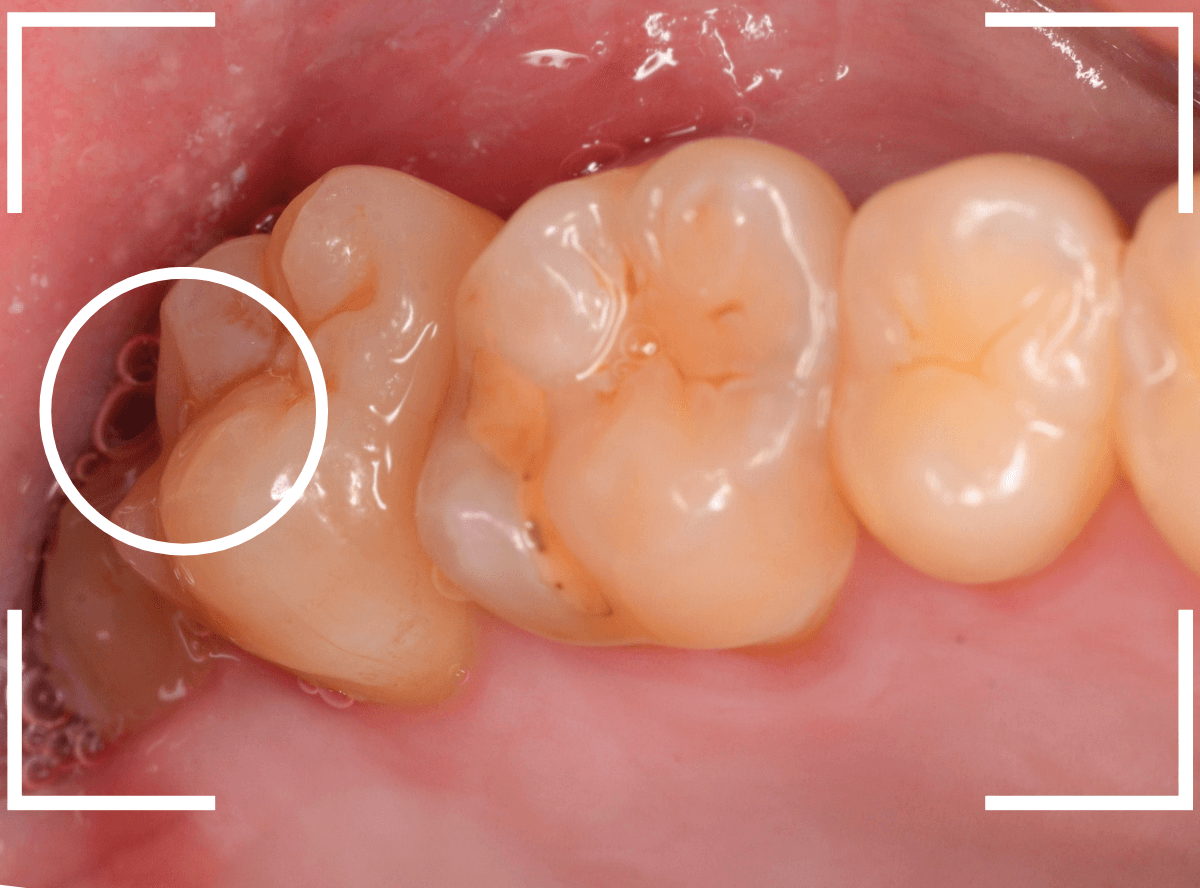

ここでは、比較的簡単なおやしらずの抜歯の例を中心にご紹介します。

このようなおやしらず、あなたはありませんか?